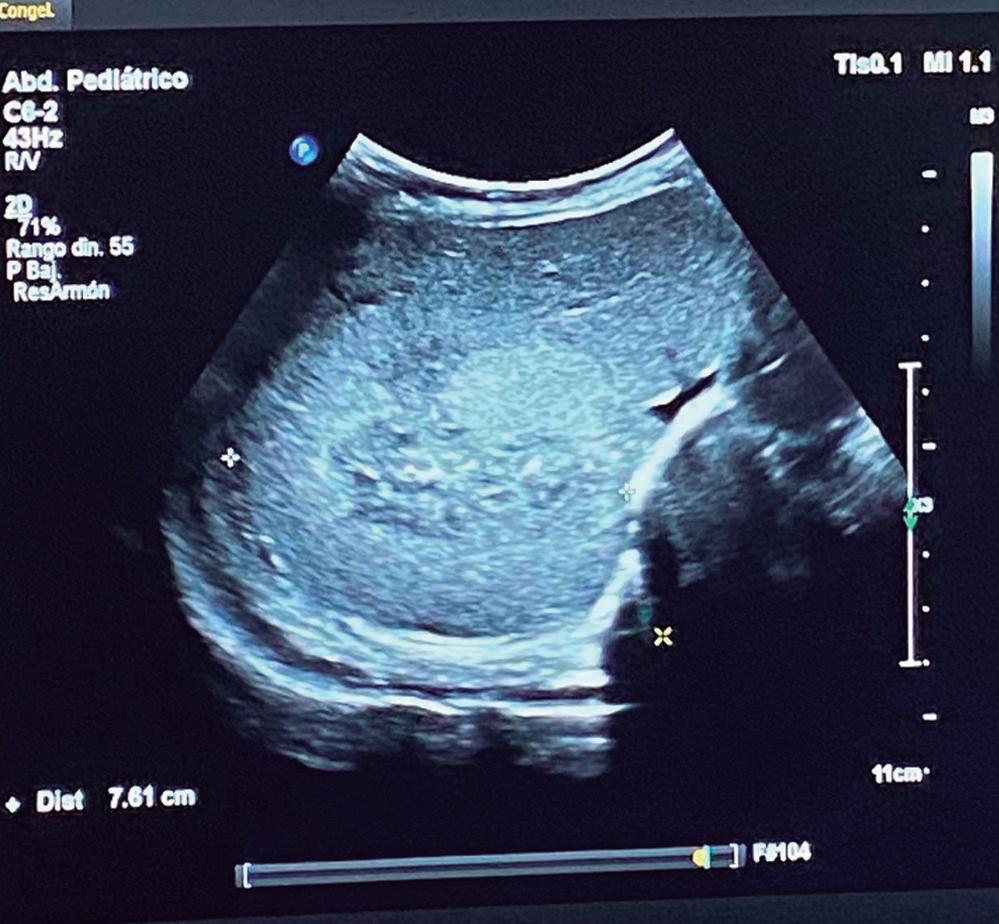

Hemangioendotelioma hepático infantil con elevación de alfa-fetoproteína: reporte de caso y revisión

María Laura Valberdi Lecce, María Cristina Arregui, Carmen Lucía Otegui Banno, Andrea Besga